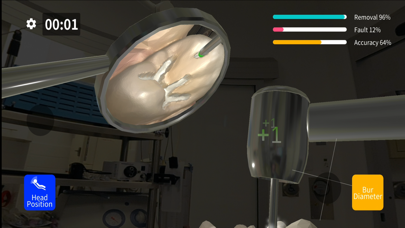

Скриншоты